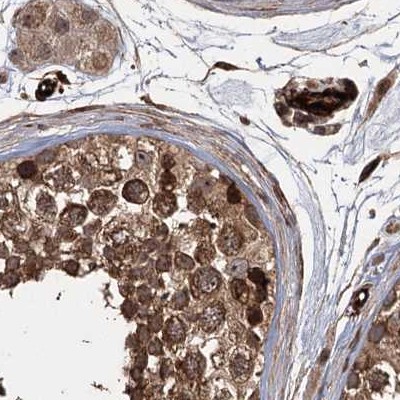

Immunohistochemical staining of human cerebral cortex, colon, fallopian tube and testis using Anti-RPAP3 antibody HPA038312 (A) shows similar protein distribution across tissues to independent antibody HPA038311 (B).